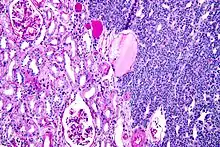

Micrograph of a metanephric adenoma (right of image). Normal kidney is seen on the left. Kidney biopsy. PAS stain.

Micrograph of a metanephric adenoma, right of image, showing the characteristic features (round nuclear membrane, no nucleoli, and fine chromatin). Normal kidney is seen on the left of the image. Kidney biopsy. PAS stain.

Metanephric adenoma is diagnosed histologically. The tumours can be located at upper pole, lower pole and mid-hilar region of the kidney; they are well circumscribed but unencapsulated, tan pink, with possible cystic and hemorrhagic foci. They show a uniform architecture of closely packed acinar or tubular structures of mature and bland appearance with scanty interposed stroma.[3][4][5][6][7] Cells are small with dark staining nuclei and inconspicuous nucleoli. Blastema is absent whereas calcospherites may be present. Glomeruloid figures are a striking finding, reminiscent of early fetal metenephric tissue. The lumen of the acini may contain otherwise epithelial infoldings or fibrillary material but it is quite often empty. Mitoses are conspicuously absent.[3][4][5][6][7] In the series reported by Jones et al. tumour cells were reactive for Leu7 in 3 cases of 5, to vimentine in 4 of 6, to cytocheratin in 2 of 6, to epithelial membrane antigen in 1 of 6 cases and muscle specific antigen in 1 of 6.[5] Olgac et al. found that intense and diffuse immunoreactivity for alpha-methylacyl-CoA racemase (AMACR) is useful in differentiating renal cell carcinoma from MA but a panel including AMACR, CK7 and CD57 is better in this differential diagnosis.[8] Differential diagnosis may be quite difficult indeed as exemplified by the three malignancies initially diagnosed as MA that later metastasized, in the report by Pins et al.[9]